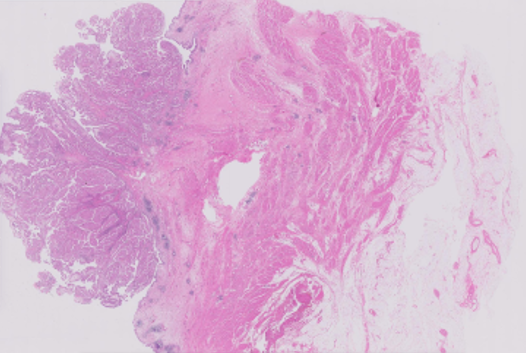

- 원천 데이터 및 Annotaion 라벨 이미지 예시

| 방광암WSI | ![]() |

![]() |

| 종양 부위와 비종양 영역을 라벨링함 |